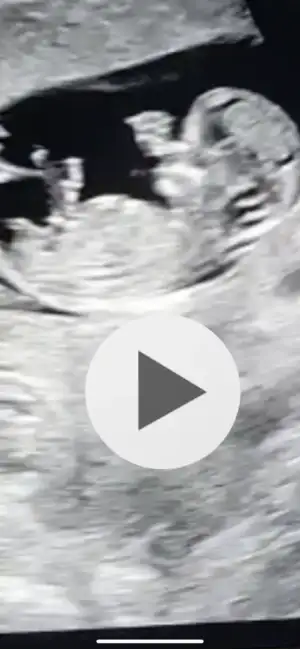

dr soylemeden siz gorun genital nub teorisi ( bebegin cinsiyeti)

Valla ne yalan söyleyim Ikra meyra Ikra meyra basta sana inanmadım 😙😊😊😀 ilk resim attığım da doktor erkek dedi sen kız dedin başka at dedin başka attığım resimlerin 4 de karından çekilmiş ben senin kız dediğini vajinal sanıyordum oda karından Mıs yanı karından sa erkek dedin sana attığım diğer resim kendi kızımın resmiydi onu sen bildin valla hakkını helal et 1 ay sonra Eğer erkekse oylamamı yapacağım 😍